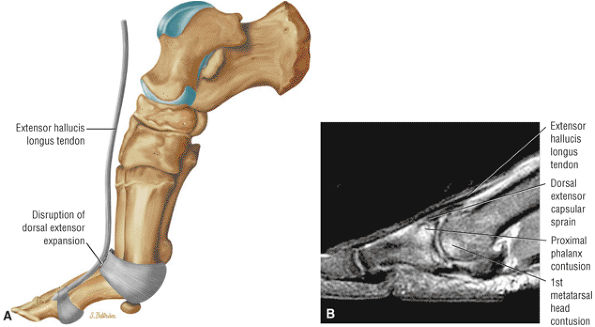

![]() |